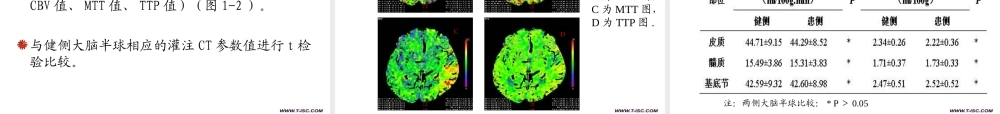

急性缺血性脑卒中灌注CT成像应用研究南通大学附属医院神经内科柯开富张元媛目录研究背景1材料与方法2实验结果3结论4研究背景对于神经功能缺损症状出现3-6小时内的急性缺血性脑卒中患者进行溶栓治疗,是目前公认的有效治疗方法,它能阻止病情进展,减轻致残程度。但如何使溶栓治疗更加安全、有效,这就需要在溶栓前对患者的脑灌注情况进行充分评估。目前对脑灌注进行评估的主要核医学技术有PET,Xenon-CT,和SPECT,此外还有功能性影像学技术,例如PWI。但是由于目前我国的现状,以及部分急性缺血性脑卒中患者因烦躁、嗜睡等原因难以配合检查,使这些影像学技术推广使用较难。灌注CT技术弥补了上述技术的不足。所以本研究的目的是探讨灌注CT技术在对脑灌注进行评估中的应用价值。材料与方法研究对象1.入选标准2.排除标准3.终止/脱落标准研究方法1.扫描方法2.患者分组入选标准收治我院的发病24小时内的颈内动脉系统急性缺血性卒中患者,均为初次发病;符合全国第4届脑血管病会议修订的诊断标准;CT排除颅内出血、肿瘤;患者意识清楚或轻度嗜睡;患者家属同意进行检查。排除标准CT证实为脑出血,或其它颅内占位性病变;轻度的神经功能损害(NIHSS<4);昏迷;严重心、肝、肾疾病;明确的碘造影剂过敏史;妊娠,近6个月有颅内出血史或手术史;患者家属不同意进行检查。终止或脱落标准患者病情恶化或死亡患者或家属要求中止检查者。常规CT扫描采用德国Siemens公司生产的16排螺旋CT扫描机(Sensation16)进行头颅平扫。所有病例在灌注CT检查前均进行常规CT扫描检查。MR扫描采用美国GE公司3.0TMRI扫描仪进行扫描。常规扫描序列包括横断面T1WI、T2WI、FLAIR,和DWI。灌注CT扫描使用德国Siemens公司生产的16排螺旋CT扫描机(Sensation16),行常规螺旋扫描后,选择基底节区或者病变所在层面(有早期缺血表现的层面)为扫描层面,经由高压注射器,经肘静脉注射非离子型造影剂,灌注CT专用软件进行图像后处理,得到一系列脑灌注参数图,包括MIP图,CBF图,CBV图,TTP图,MTT图。在参数图上选取感兴趣区域(ROI),计算出ROI内各参数平均值,进行定量分析。患者分组一般认为DWI显示为高信号,或CT平扫显示为低密度的脑组织区域已经发生不可逆的神经功能缺损。所有入选患者入院1周内均进行MRI检查,或常规CT平扫复查。结合患者1周内MRI或CT平扫检查结果,将患者入院时的灌注CT图像进行分区。梗死区DWI显示为高信号,或常规CT平扫显示为低密度的脑组织区域梗死周...